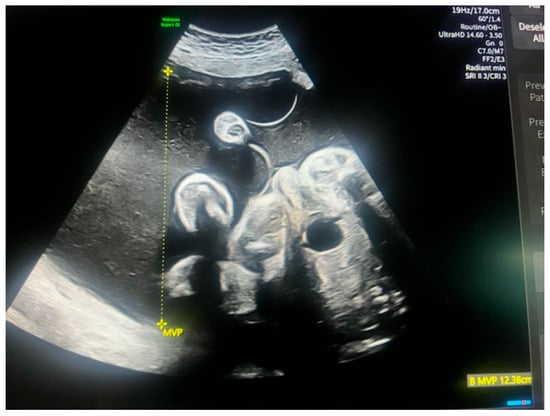

Prenatal Diagnosis of Acrania in One Twin of a Dichorionic Diamniotic Pregnancy: A Case Report on Management and Perinatal Outcome

2. Case Presentation